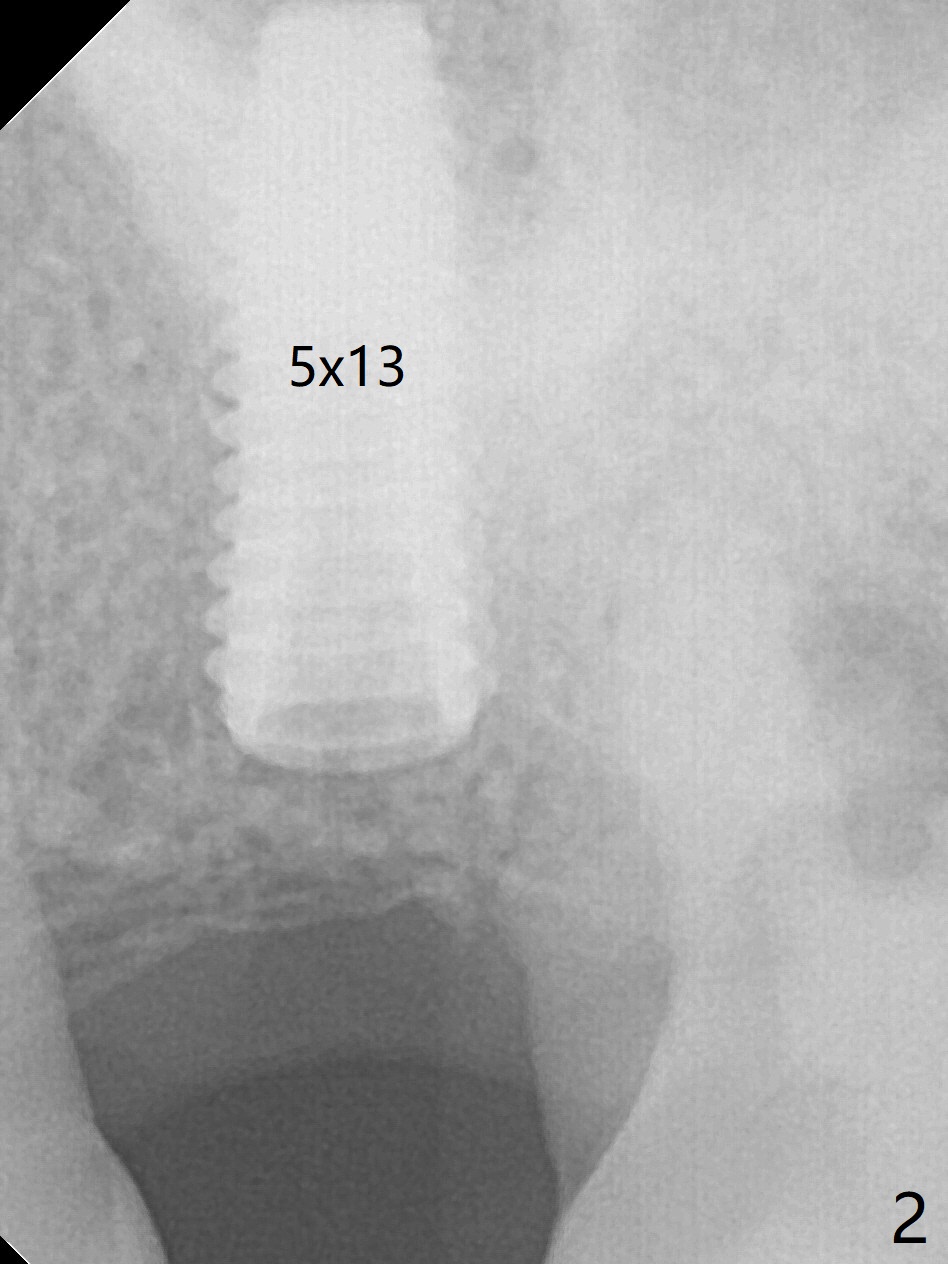

The patient is extremely nervous about implant placement at #14. Access is obtained with a 4 mm tissue punch, which appears to be the least traumatic. Since the gingiva is ~ 5 mm thick, vision is poor and it is difficult to change osteotomy buccally. It seems a 6 mm tissue punch is more appropriate for this case. The initial osteotomy depth is 14 mm (Fig.1). Since the tooth #15 is nonsalvageable because of furca caries and bone loss (Fig.1 *), the distal osteotomy at #14 is apparently acceptable. When a 5x13 mm implant is placed with >50 Ncm (Fig.2), the implant is subcrestal clinically except palatal (osteotomy not buccal enough), which is consistent with bitewing view (Fig.3). A 5.5x5 mm healing abutment is placed. Surprisingly the fearful patient does not experience any pain. Tissue punch is an atraumtic measure. A larger one (6 mm) allows more room to change osteotomy. The access can be closed with larger healing abutment. If this implant fails due to periimplantitis, it is due to palatal placement with too large the implant (5 mm vs. 4 mm at #3). Palpate the bone prior to changing next large drill when performing a flapless procedure. The implant seems to be osteointegrated 5 months postop; the furca caries (Fig.4 *) is taken care of before impression with a 4.5x5(4) mm abutment. Distal caries of the tooth #13 is found 10 months post cementation (Fig.5). Strict oral hygiene for prevention should have been given after composite for the furca of the tooth #15 (*).